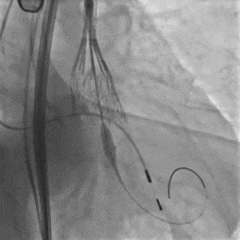

根部造影,可见大量反流

第一次展开,瓣膜形态敞口

第二次展开,瓣膜位于0位;此时患者发生室颤,除颤后进行按压

瓣膜按压后位置发生变化

多体位观察

瓣膜位于瓣上,选择回收